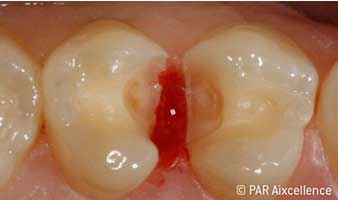

Abb 3: Bei der Anfangseröffnung ist die Karies deutlich klinisch sichtbar.

Abb 4: Bild wie Abbildung 3 - diesmal unter Anwendung von Facelight.